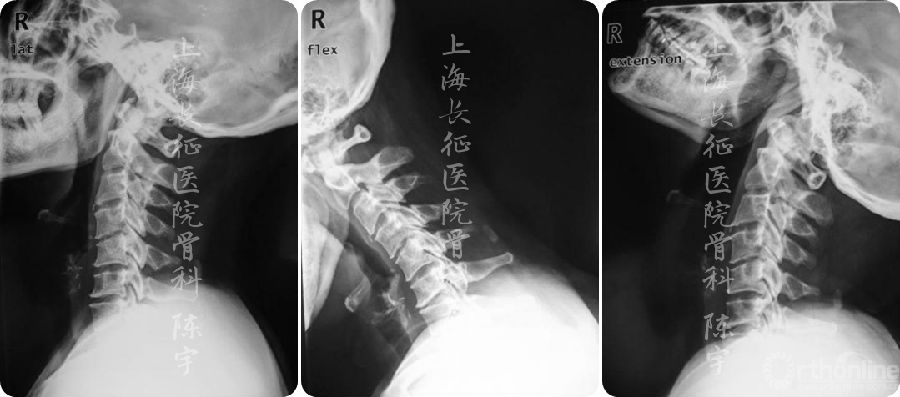

术前影像学检查(图1):

(1) X线:颈椎侧位及伸屈侧位片显示颈椎呈后凸畸形;

(2) MRI:颈4-6水平脊髓严重受压;

(3) CT: 颈4-6连续型后纵韧带骨化,在最严重水平椎管狭窄率达到90%以上,在横断面上表现为典型“双影征”,提示合并硬膜囊骨化。